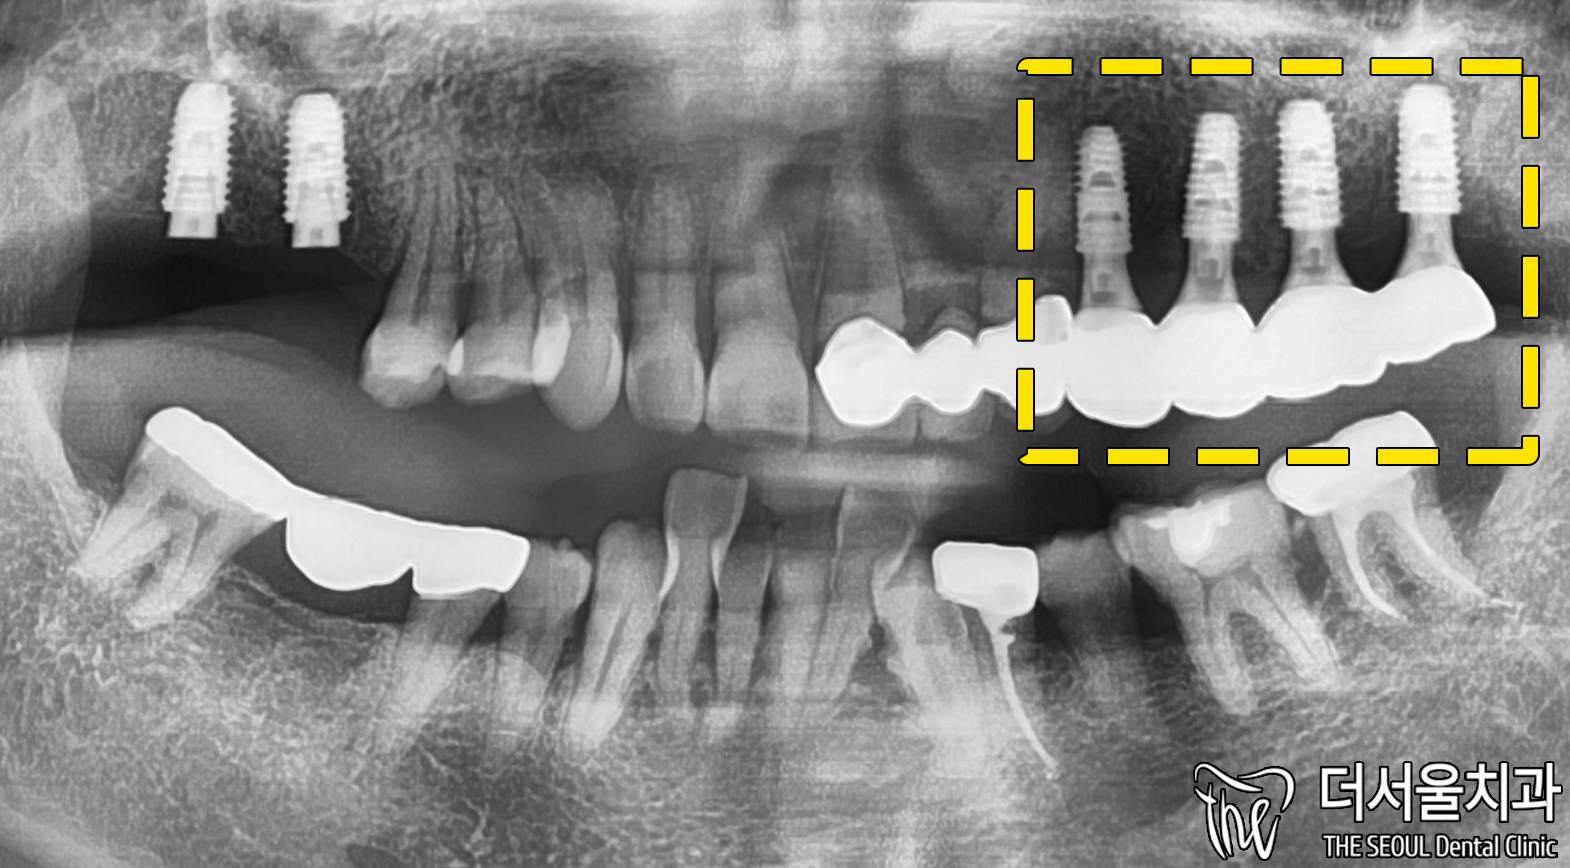

3개월 뒤, 왼쪽에 심어놓은 것들이

먼저 적합한 ISQ 수치를 가지게 되었습니다.

아무래도 오른쪽은 골밀도가 낮았기에

그만큼 더 시간이 걸릴 수밖에 없었던 거겠죠.

왼쪽 먼저 인상 채득을 해준 뒤,

맞춤형 보철을 제작하며 최종 세팅까지 했습니다.

맞춤형을 추천 드리는 이유는

그만큼 관리하기에 용이하며,

관리가 잘 되는 만큼

수명이 더 늘어나기 때문이죠.

이렇게 세팅이 다 끝났다 하더라도

좀 더 안정될 수 있도록 조심하는게 좋다 알려드렸습니다.